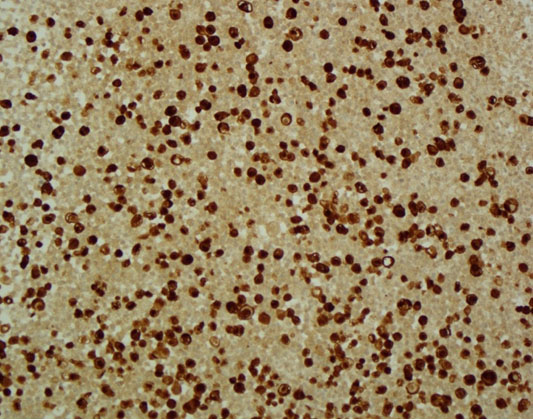

The patient was admitted to the hepatology inpatient service with consults from rheumatology, infectious disease, hematology, nephrology, pulmonology, and interventional radiology for a multidisciplinary approach to management. He underwent paracentesis followed by thoracentesis and an ultrasound guided peritoneal nodule biopsy. Turbid white chylous fluid (1200 mL) was removed from the left chest. The initial clinical impression from pulmonary was that the bilateral chylous effusion was likely secondary to superior vena cava syndrome and left brachiocephalic obstruction caused by lymphadenopathy. He was commenced on a low cholesterol diet and nutrition was consulted. Laboratory results from the first peritoneal tap showed atypical mesothelial cells indeterminate for malignancy (Figure 2). Subsequent thoracentesis (Figure 3) and paracentesis (Figure 4) specimens had higher cellular yield and revealed highly atypical mesothelial cells with high nuclear to cytoplasmic ratios and prominent nucleoli suggestive of malignant mesothelioma. Tumor cells were immunoreactive with Calretinin immunohistochemistry stain (Figure 5) which supported mesothelial origin rather than an epithelial origin (carcinoma). The diagnosis was further confirmed by an ultrasound guided peritoneal nodule biopsy which showed a consolidation of epithelioid tumor cells consistent with malignant mesothelioma, epithelioid type (Figure 6). Immunohistochemical staining of the omental biopsy for Ki 67 staining showed a high proliferative index > 10% (Figure 7). The tumor also contained foci of inflammatory cells including many plasma cells. These inflammatory cells could be reactive to the tumor or related to an underlying autoimmune or inflammatory process.

Figure 5: Peritoneal fluid with tumor staining for Calretinin (cell block, low power).

Share Image: